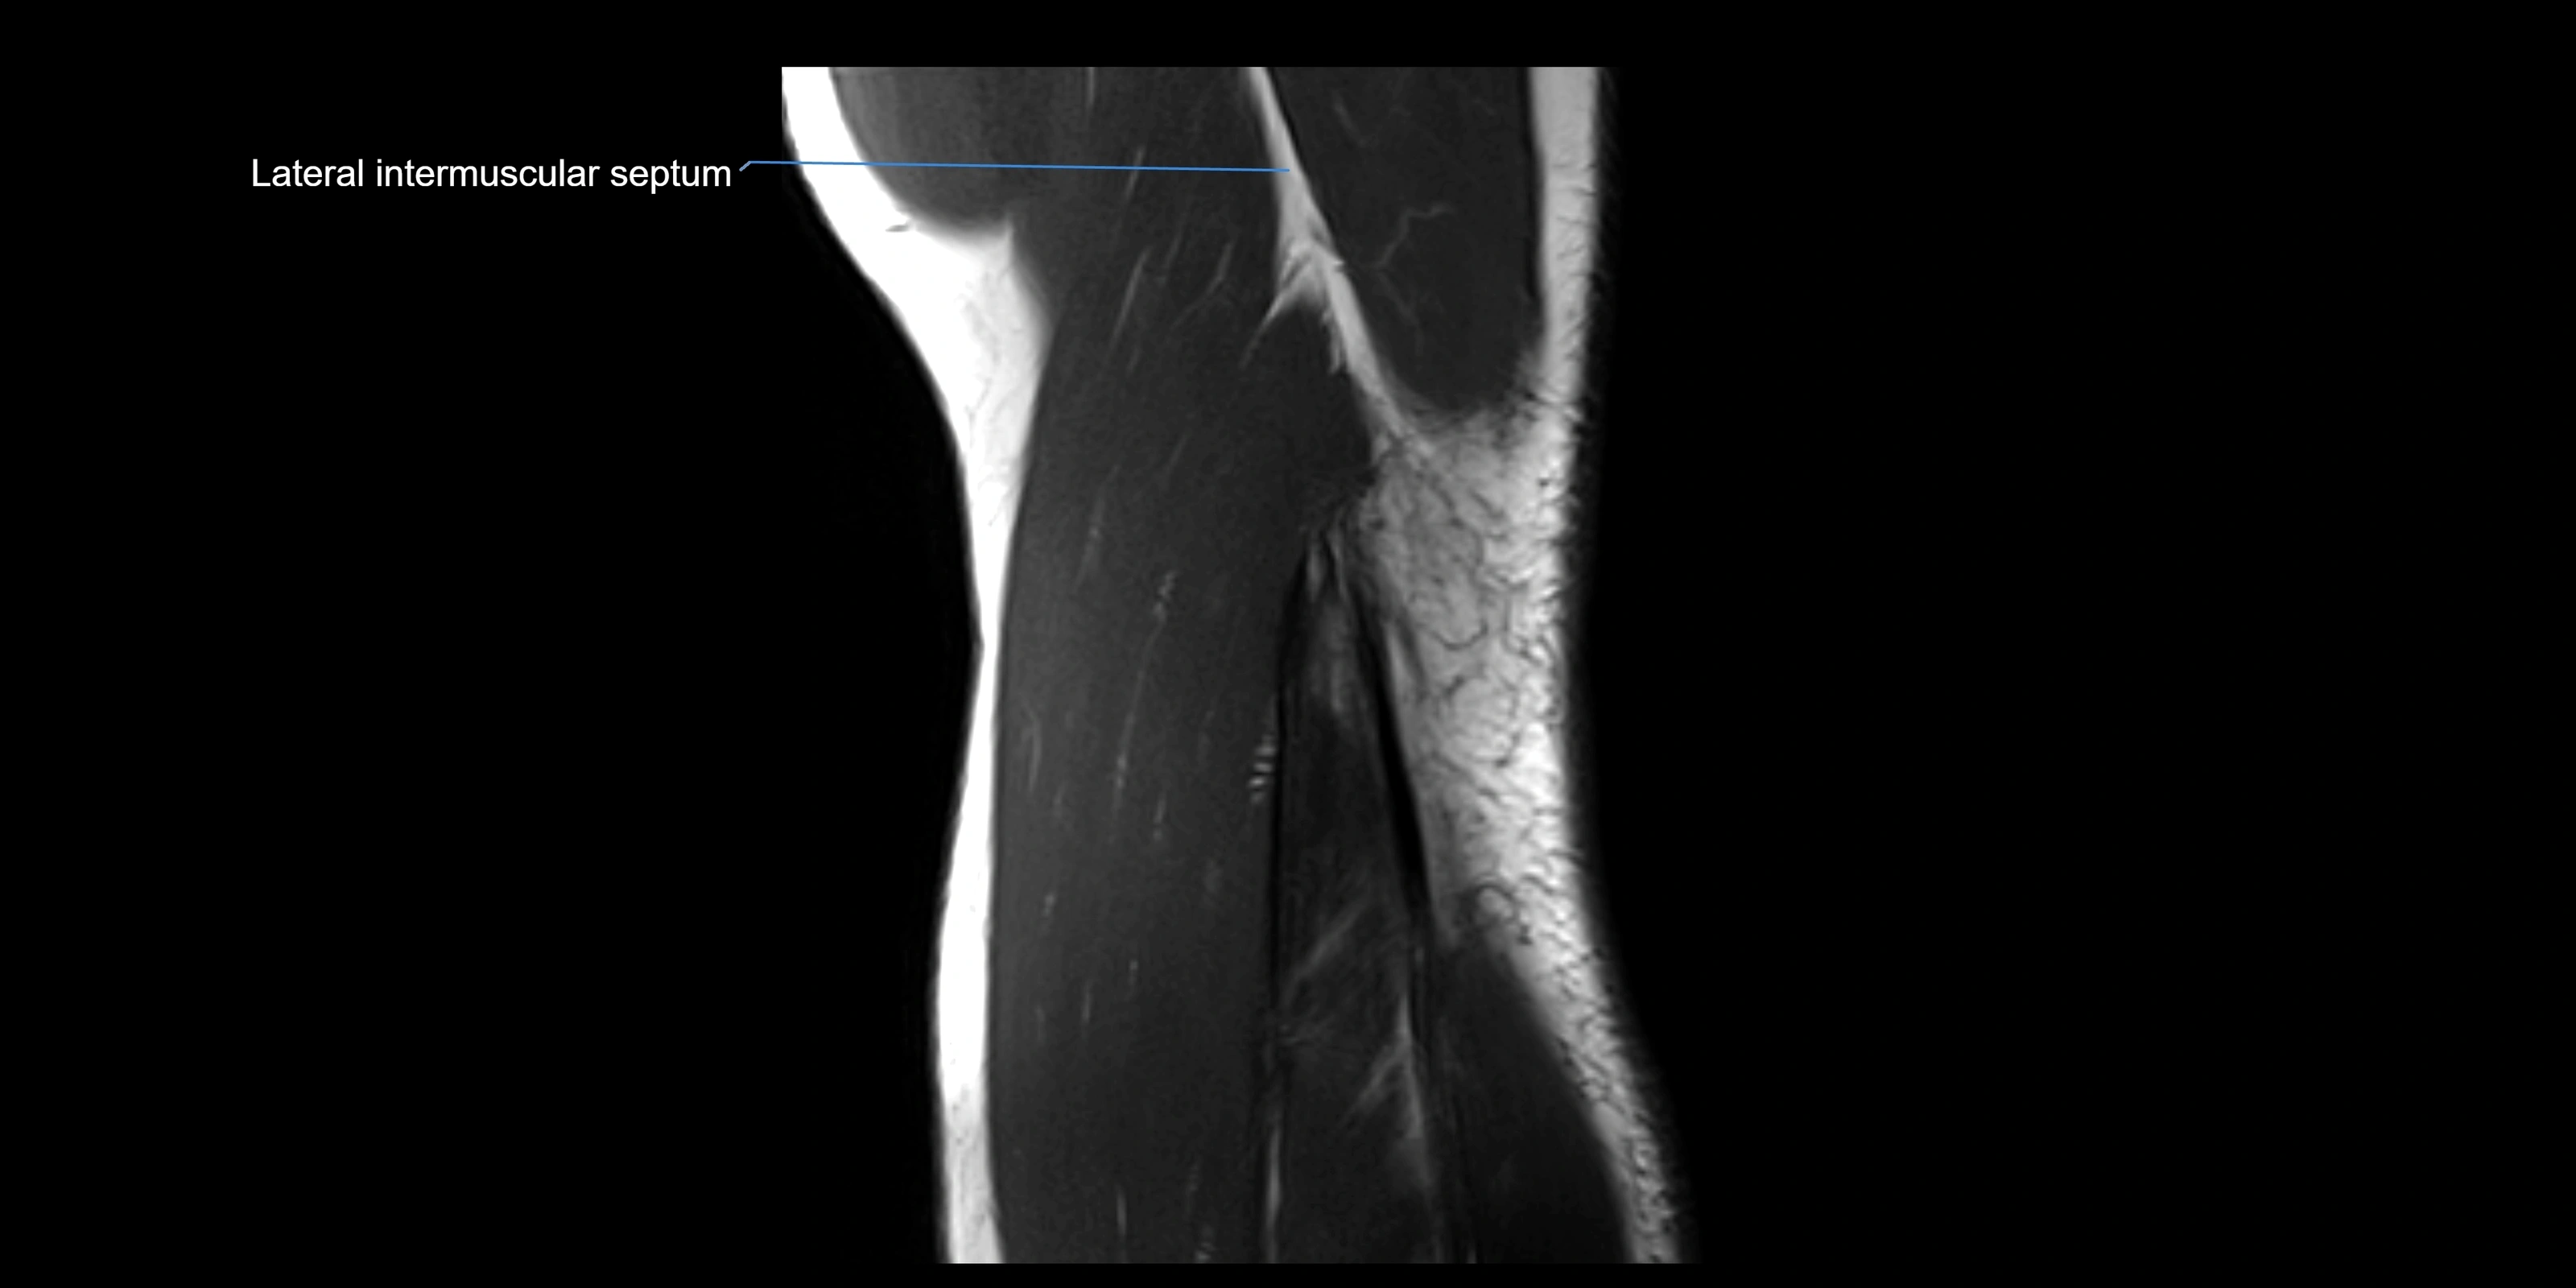

MRI images

image